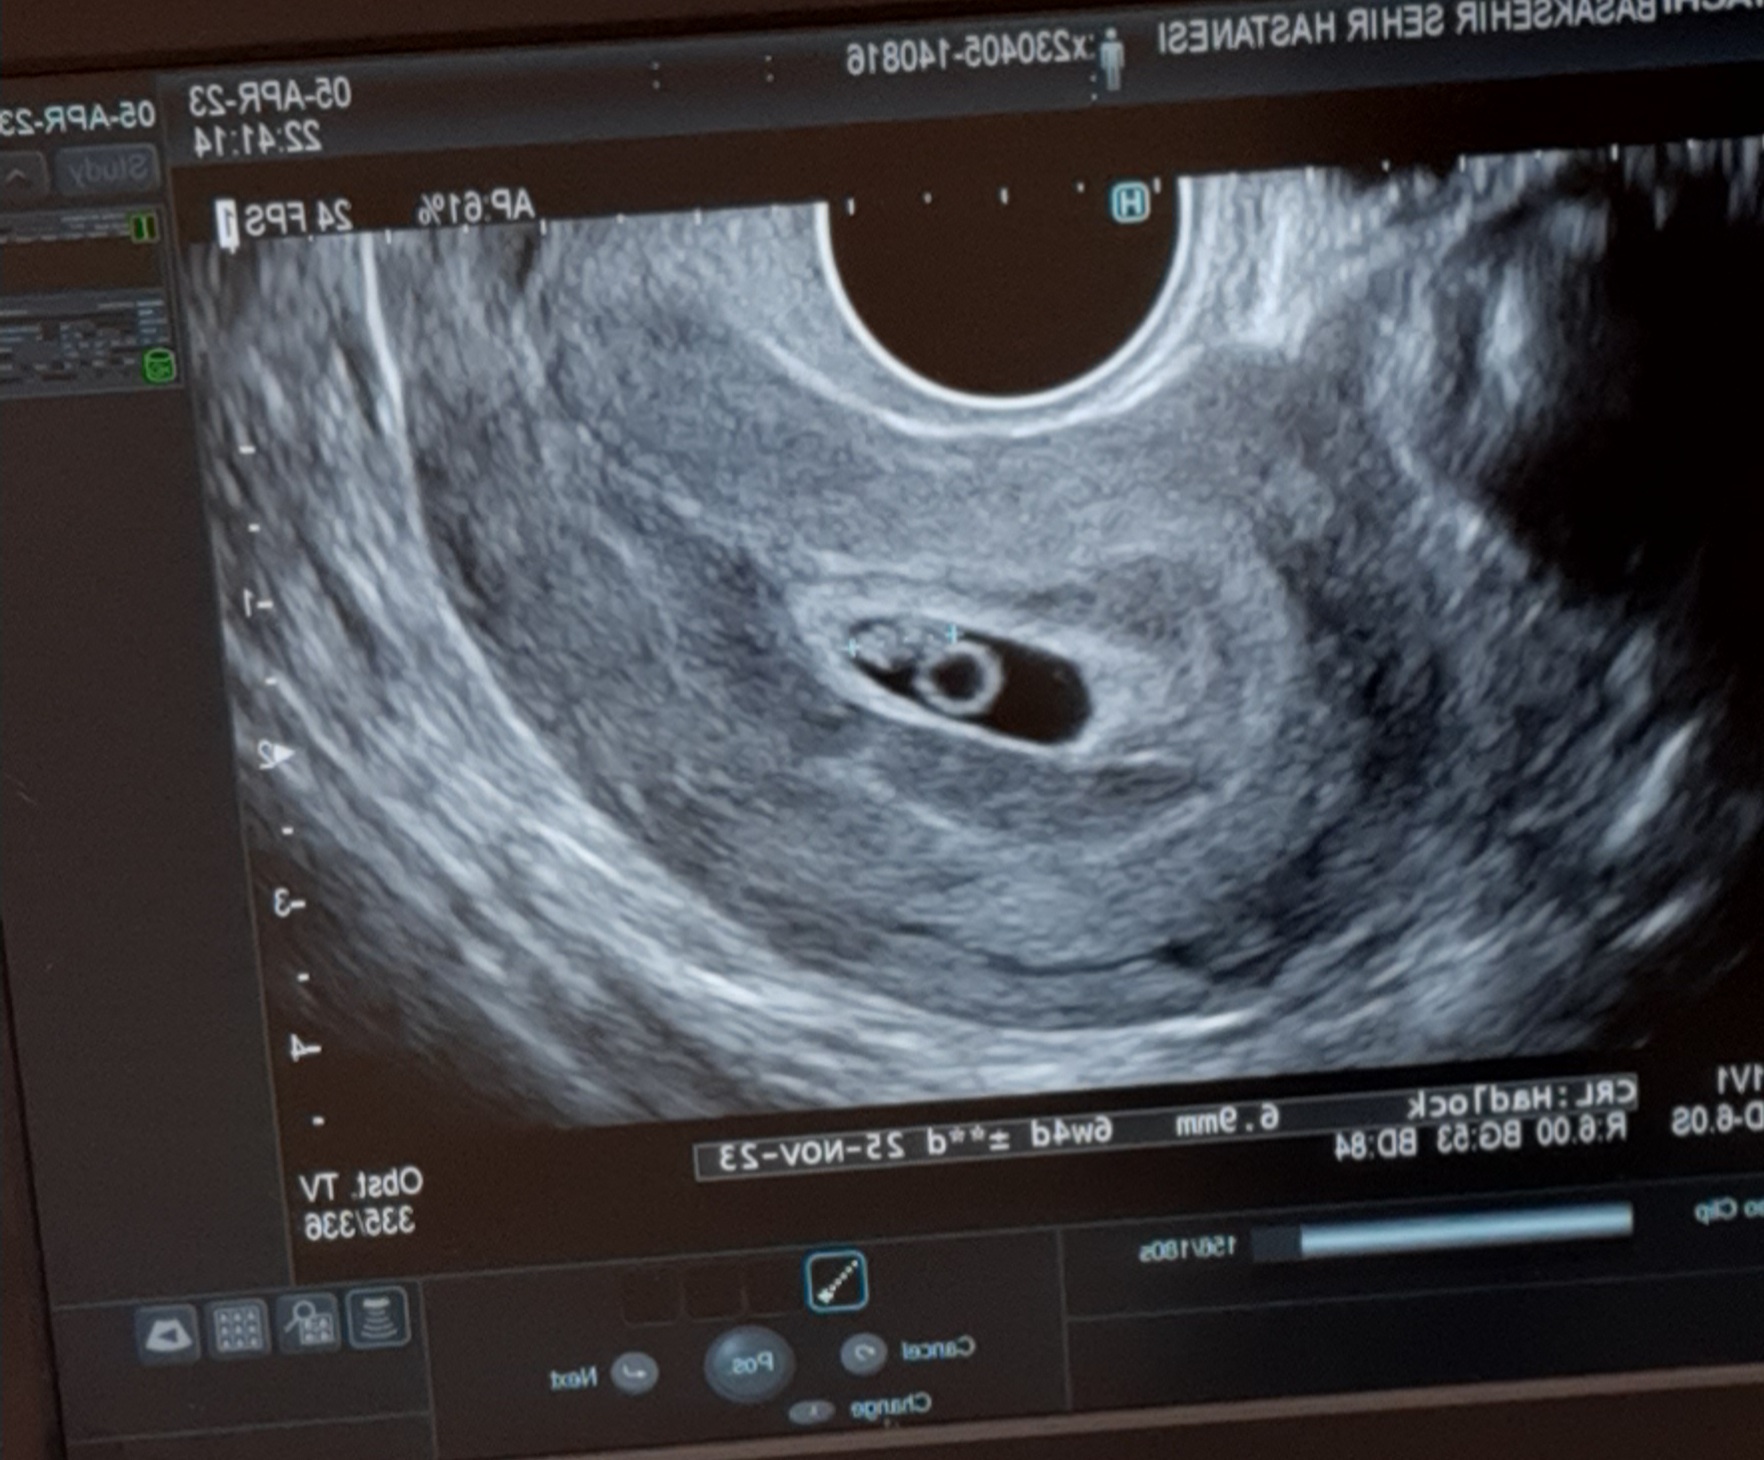

Kızlar gittim progestanı 2 katına çıkardılar kanama devam ederse hemen geri gel dedi doktor çok şükür bebeğim iyi ♥️ Bu da Minik Bebeğimin ilk resmi🥰Ekli dosyayı görüntüle 3795

Baştan resim eklemedim yeni ekleyebildim bu şekilde kızlar özür diliyorum öncelikle kızlar merhabalar kahverengi olan akıntım artık çokça artmaya başladı kana döndü artık pıhtı atıyor resmen progestan ve aspirin de kullanıyorum ama maalesef bir faydasını göremedim acaba acile gitsem yatış yapılır mı kızım da var aklımda onda kalıyor ama bu bebeğimi de kaybetmek istemiyorum kaç gündür gitmedim hastaneye kalp atışı varsa yatış yapılır mı sizce başakşehir çam sakuraya gidebilirim bilen bilir o hastaneyi.